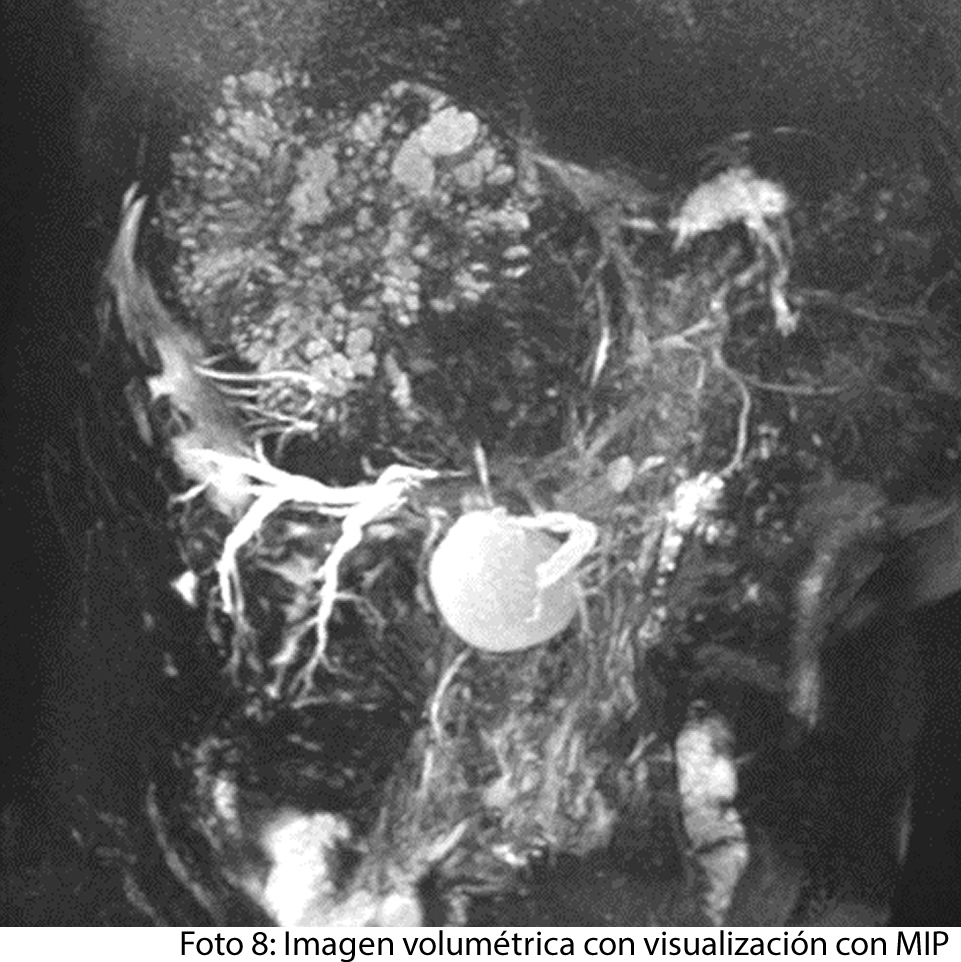

TECNICA EMPLEADA

Se procede a atender a paciente luego de cumplir con los protocolos para la realización de estudios de resonancia, paciente ingresa a zona 4, se coloca en posición decúbito supino, se utiliza gating respiratorio, estudio se obtiene con uso de bobina phase arrays, PSP Axial, sagital y coronal, secuencias Se y Gre, ponderadas a T1 y T2, se administra medio de contraste hepato especifico y se utiliza protocolo para estudio dinámico.

HALLAZGOS IMAGENOLOGICOS

• HEPATOCARCINOMA FIBROLAMINAL QUE COMPROMETE TODO EL LÓBULO DERECHO DEL HÍGADO

Es un método utilizado en el cual podemos observar una gran masa localizada en los segmentos del hígado también se puede medir el diámetro de la masa, el hepatocarcinoma también puede presentar focos hemorrágicos y además podemos captar de manera heterogénea el medio de contraste intravenoso. En los hepatocarcinomas podemos ver obstruyendo parcialmente la vena porta. Adenomegalias los cuales nos indican Los hallazgos como primera posibilidad diagnóstica, carcinoma hepatocelular fibrolamelar (CHC-FL).